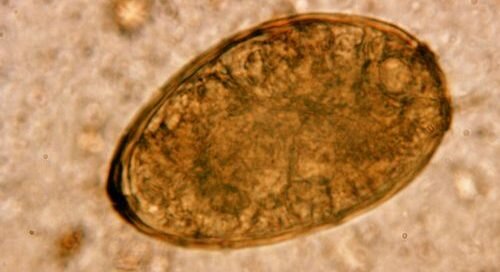

К этому классу относятся плоские паразитические черви человека и животных. Существует около 6000 видов трематод. На брюшной стороне тела гельминтов есть 2 присоски – ротовая (для питания) и брюшная (для крепления). Жизненный цикл всех видов трематод проходит со сменой хозяев. Половозрелые гельминты обитают в крови, кишечнике, печени, лёгких, пищеварительном тракте.

Размеры трематод могут варьироваться от 2 мм до 8 см в длину, форма тела у большинства видов листовидная. Некоторые представители имеют почти круглую форму. Тело покрыто тегументом – особым видом эпителия, обеспечивающим защиту паразита от воздействия пищеварительных соков хозяина.